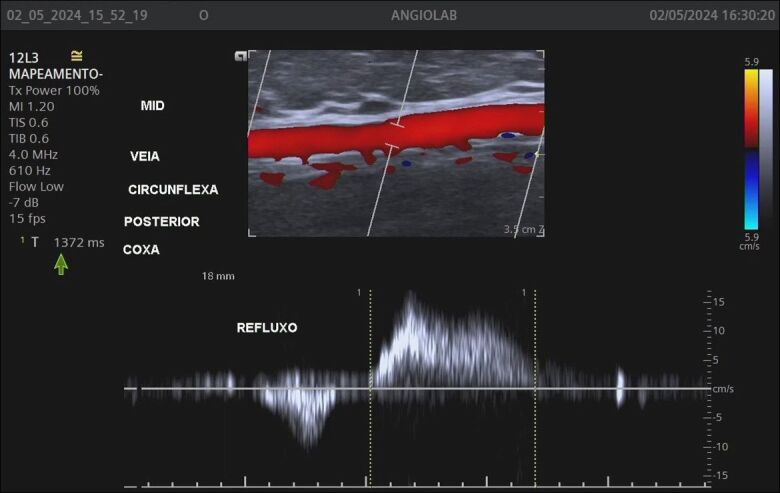

Background: The Giacomini vein (GV) can transfer reflux from perineal veins, tributary veins, and perforators of the thigh to the small saphenous vein (SSV). Vascular ultrasound with Doppler (VUD) is the preferred method for detecting reflux in specific veins such as the GV.

Objective: To identify GV depth and diameter, reflux in the GV, and presence of reflux in the SSV caused by the GV.

Methods: A cross-sectional, retrospective study was conducted in women undergoing lower limb venous mapping for varicose vein surgery. The following parameters were analyzed in GVs in which reflux was detected: segmental or diffuse reflux pattern; GV diameter and depth; and reflux in the SSV caused by the GV.

Results: 340 of the 2368 women evaluated were included in the study because they had a GV, totaling 511 veins analyzed, 150 (29.4%) of which had reflux. The diameters of the 150 GVs with reflux ranged from 1.5 to 7.8 mm and their depth varied from 4 to 25 mm. Most GVs with reflux (91.3%) had a segmental reflux pattern. The majority (66%) of refluxing GVs drained reflux into the popliteal vein through the saphenopopliteal junction, while reflux was transferred to the SSV in 34 veins (22.7%), and was drained by a tributary vein in the thigh in 15 veins (11.3%).

Conclusions: Approximately one-third of the studied GVs had reflux, mostly segmental, mean caliber was 2.7 mm, and mean depth was 11 mm. Reflux in the SSV originating from the GV was detected in 22% of the evaluated veins.